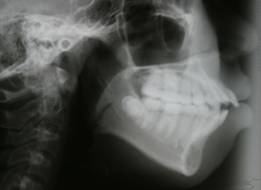

セファロレントゲン(矯正前)

|